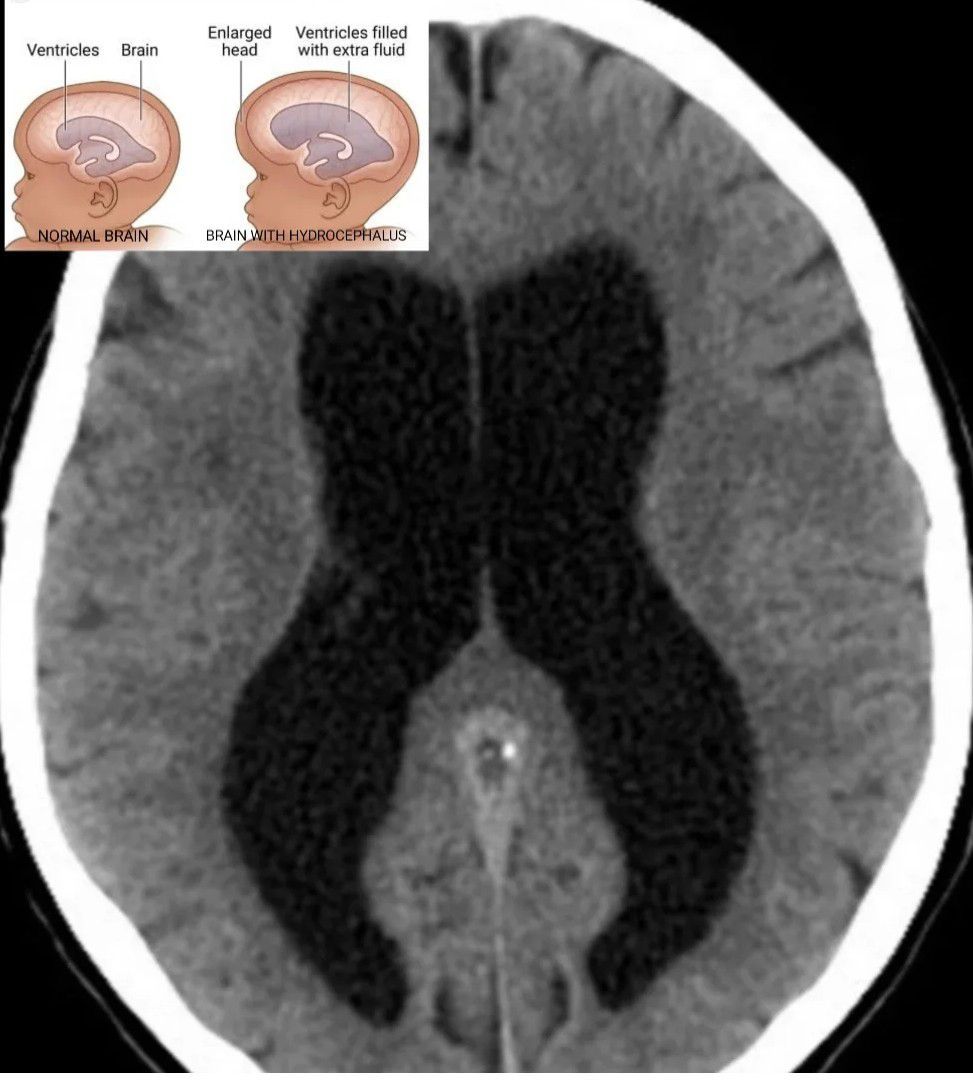

Hydrocephalus

Hydrocephalus is a condition in which cerebrospinal fluid builds up within the brain, which can cause pressure to increase in the skull. Symptoms may vary according to age. Headaches and double vision are common.